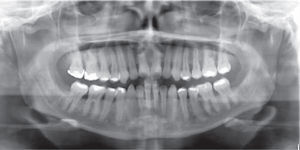

A panoramic radiograph was obtained to reposition the brackets accordingly. The brackets form teeth #42 and 35 were repositioned to achieve root parallelism.

After bracket repositioning, a space opened between the lower right lateral incisor and canine and reseated so the SKL archwire was placed again to close that space (Figure 7C); four months after, the fixed appliances were removed (Figure 8). As retention a circumferential retainer was placed in the upper arch, while a fixed retainer made with a 0.0175” braided wire and bonded with fluid resin was placed in the lower (Figure 9).

RESULTSThe arches were successfully correlated by eliminating the crossbite, the crowding was solved and the spaces were closed thus improving occlusal relationships and achieving molar and canine class I. The resulting overbite and overjet were adequate and remained under control. Periodontal status, aesthetics and function were favored (Figure 10) so the oral health and facial status of the patient was improved (Figure 11), emphasizing the harmony of a beautiful smile (Figure 12).

In the final cephalometry and in the superimposition, the skeletal changes were: initial facial depth: 94°, final: 92°; initial maxillary depth: 94°, final 95.4°; initial convexity: 0mm, final: 3.2mm; initial facial axis: 89°, final: 92.6°; initial Gn-GN/L1: 88°, final: 89°; initial SN/ U1: 100°, final 115° (Figure 13). It may be observed that a conservative treatment was performed since no surgical procedure was needed to correct the skeletal problem in addition to controlling periodontal health and improving the patient's esthetic conditions. However in order to achieve these results, the upper incisors were proclined (Figure 14).